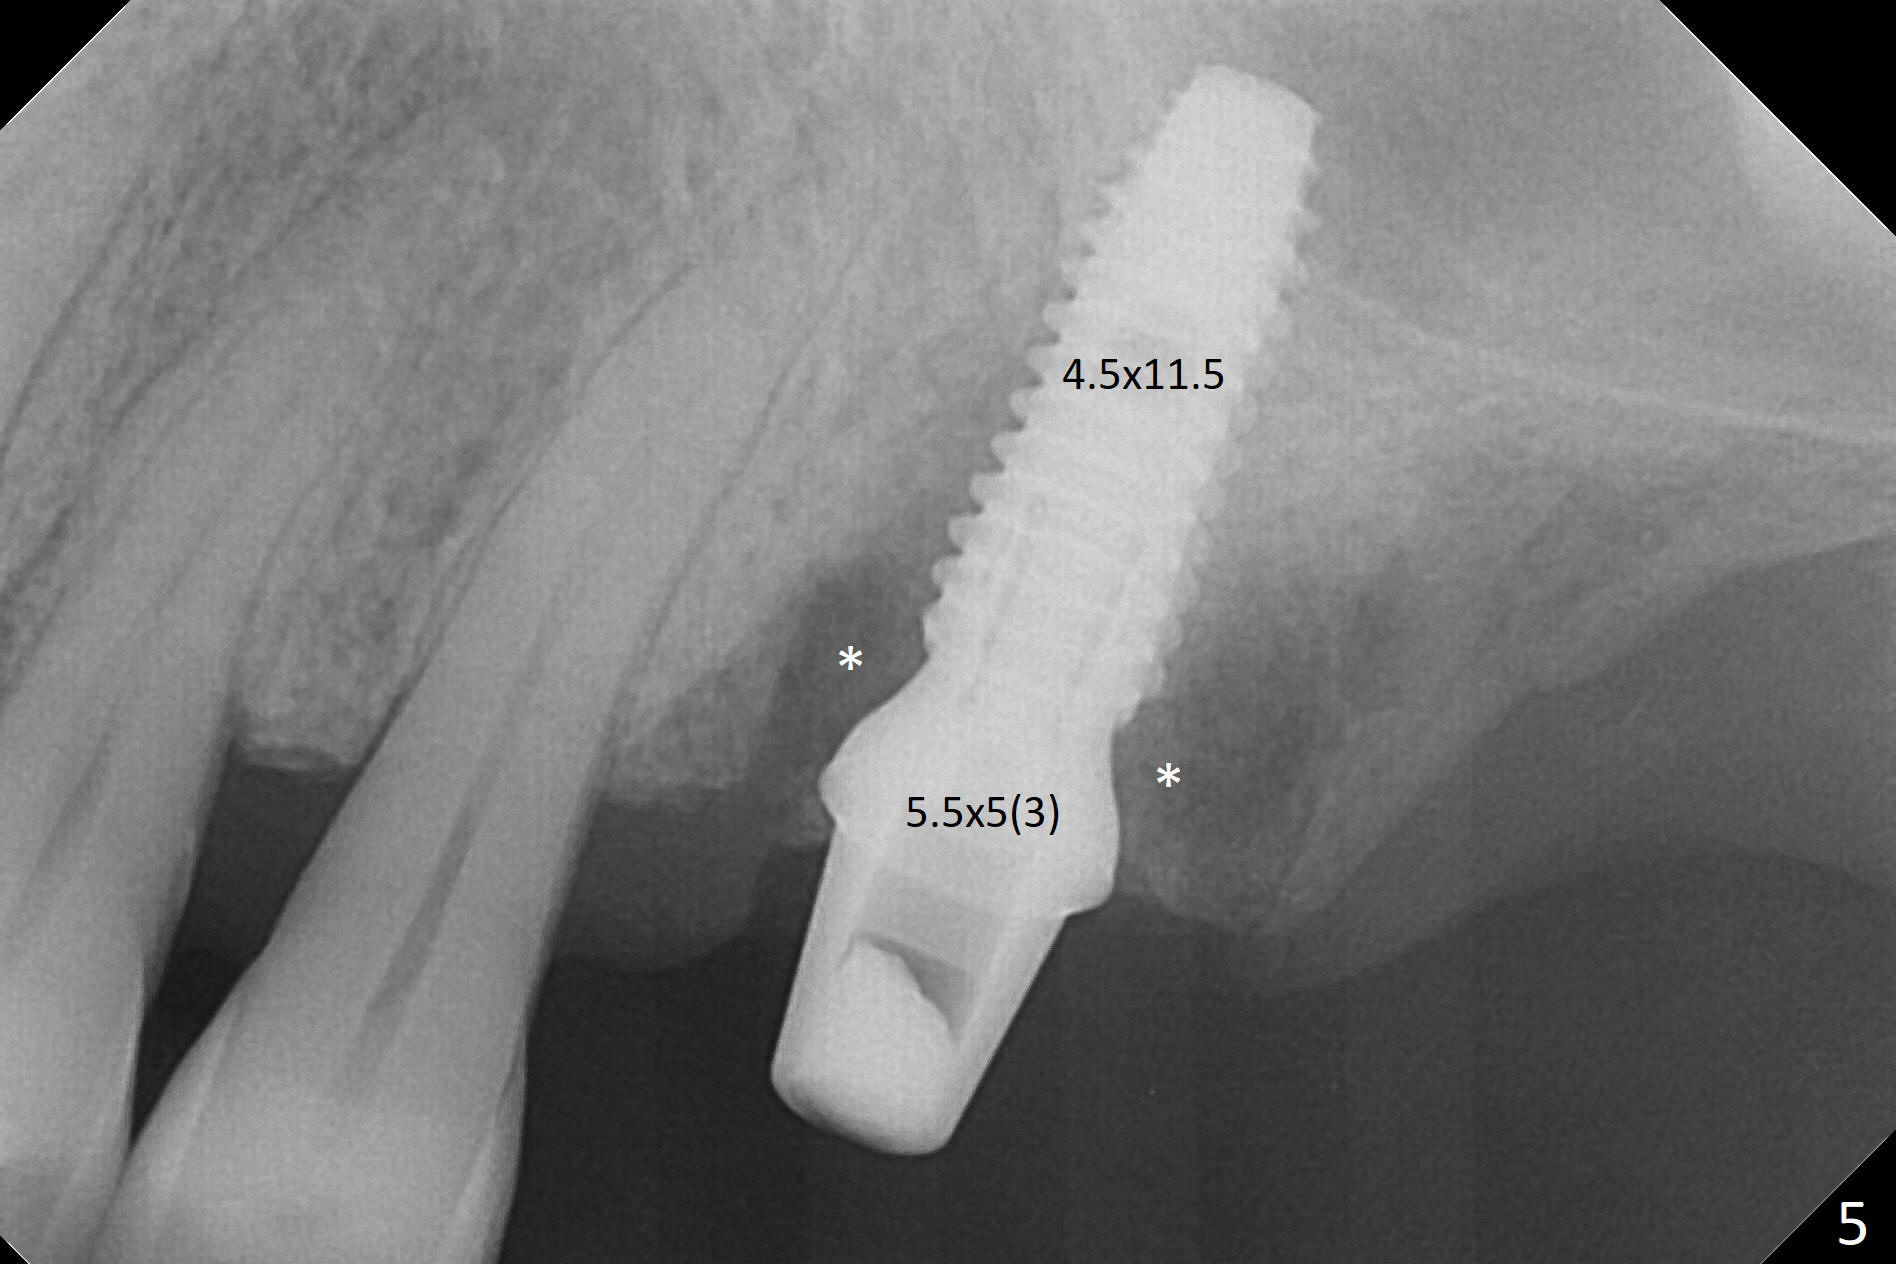

Buccal gingival recession at #14 (Fig.1) is less severe than the palatal one (Fig.2). Without raising the buccal gingiva (Fig.3 B), osteotomy in the septum is established apparently in the middle socket (Fig.3 *, 4). As the osteotomy increases with 3.8 mm drill, the palatal wall of the osteotomy starts to be perforating. When a 4.5x11.5 mm implant is placed, palatal threads are exposed, to which autogenous bone and Vera Graft are placed (Fig.5 *). After placement of a 5.5x5(3) mm abutment, an immediate provisional (Fig.6 P) is fabricated to cover the sockets. If the septal dimension were studied carefully by raising the buccal gingiva slightly, the osteotomy could be initially more buccal so that the palatal thread exposure could be less. When the provisional is removed 1.5 months postop, the implant is exposed palatally. The margin of the provisional is modified so that the implant can be cleaned by the patient using Water Pik. In fact, the healthy gingiva seems to be attached to the implant threads 2 weeks later (Fig.7). The distal implant threads remains exposed 6 months postop; it appears that the distal socket wall has resorbed (Fig.8). The sockets heal 1 year 7 months post cementation (Fig.9).